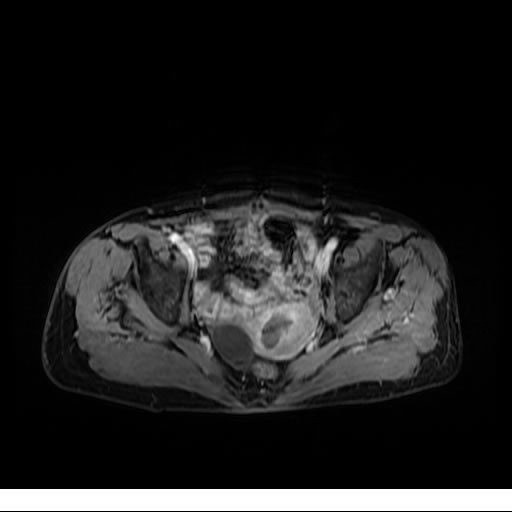

Se realizan adquisiciones en diferentes planos, con secuencias Spin echo y GRE, ponderadas a T1 y a T2, se utilizan pulsos de saturación de grasa y se administra medio de contraste a base de gadolinio.

El útero está en retroversión, retroflexión, y en posición central, se observa liquido en la cavidad endometrial, debido a la presencia de un Ca endometrial; en el anexo derecho se observa una masa quística que mide 3.8 x 2.2 cm de diámetro, corresponde a un quiste bilobulado, posee pared gruesa con componente solido puede tratarse de un Cistoadenocarcinoma, el cual realza con el medio de contraste de forma importante, entra dentro de una clasificación O-Rad tipo IV compatible con un Cistoadenocarcinoma

O-RAD tipo IV, Cistoadenocarcinoma